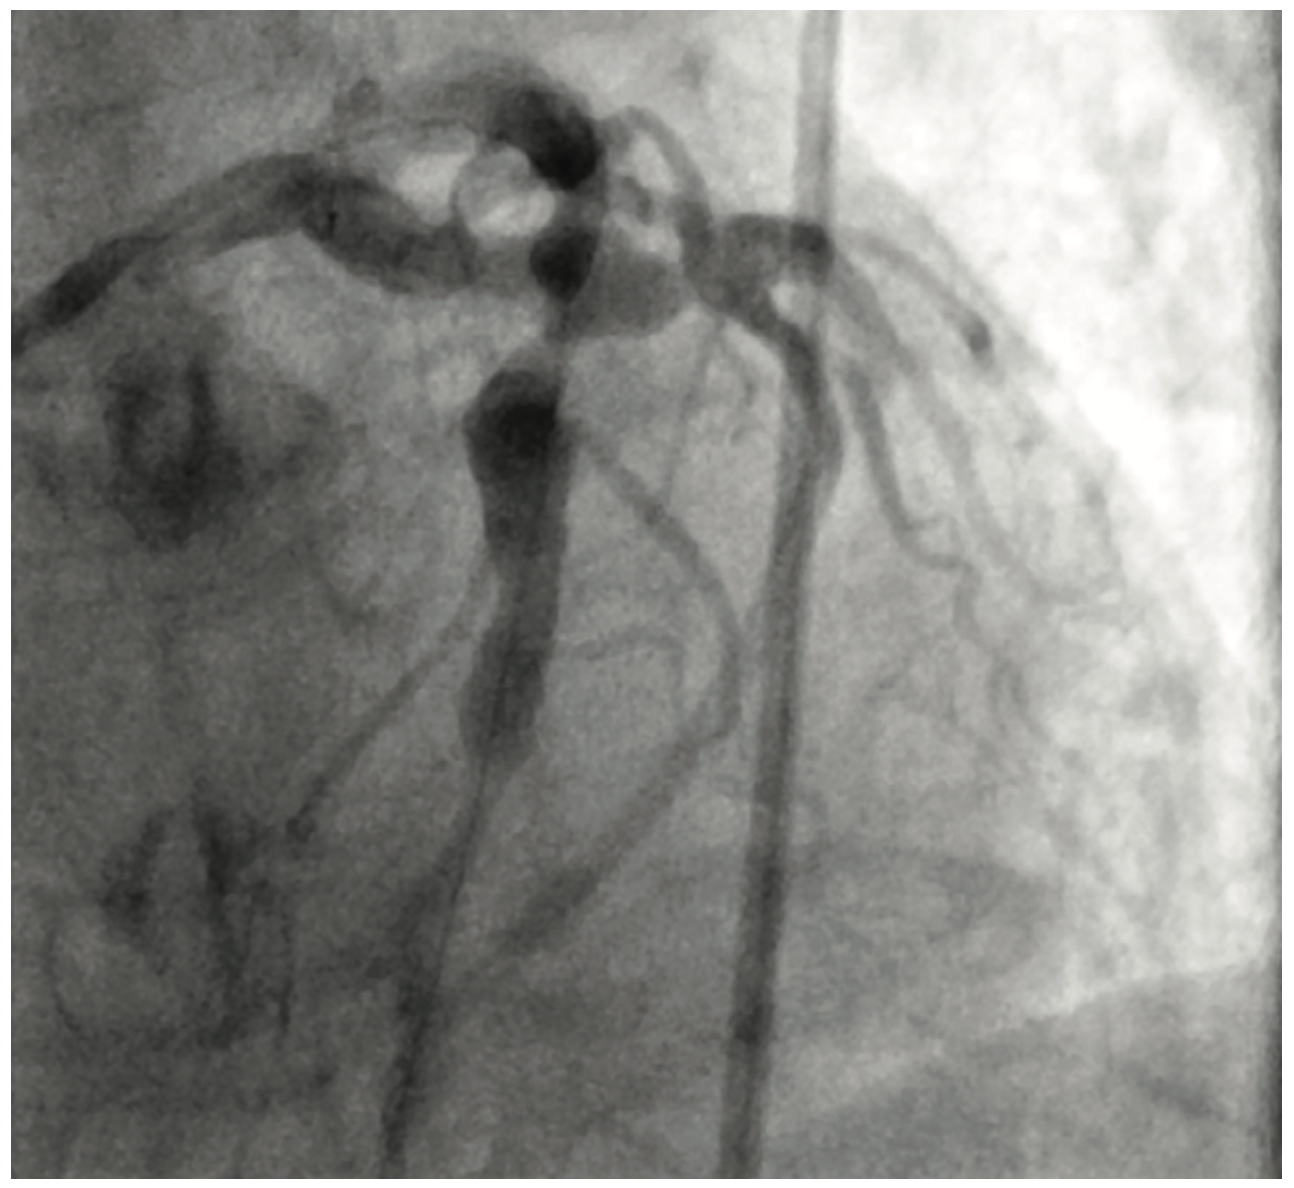

Figure 3. Giant coronary aneurysms throughout LAD and LCx.

Cardiac catheterization showed total occlusion of the left anterior descending artery (LAD) with multiple coronary aneurysms in the LAD, left circumflex (LCx), and right coronary arteries. There was TIMI 0-1 slow flow within the coronary aneurysms. An eptifibatide bolus and drip was started. Aspiration thrombectomy using an Export catheter (Medtronic) and then rheolytic thrombectomy using an AngioJet catheter was performed on the proximal and mid LAD. A 4.0 x 16 mm bare metal stent was placed. However, the patient became hypotensive in the cath lab and a balloon pump was inserted. Prior to leaving the lab, there was resolution of the ST segment elevations. The patient was started on both a heparin drip and low-dose dopamine drip.

Coronary artery aneurysm presents itself in three ways: saccular, fusiform, and mixed arteries. In the case of our patient, he had both fusiform and saccular coronary aneurysms. Most frequently, giant coronary artery aneurysms are found in the left anterior descending artery, while manifestation in the left main is rare.6,7 Patients can present as asymptomatic or symptomatic. Symptoms can include ischemic or heart failure symptoms such as angina or dyspnea.